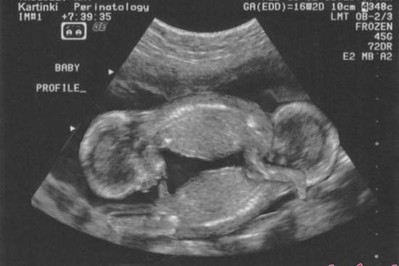

Zanim moja córka została mamą poroniła dwukrotnie. Bardzo to przeżyłam, bo chciałam zostać babcią i czekałam na wnuki. Kiedy Patrycja po raz trzeci zaszła w ciążę była pod stałą opieka lekarza a 3 miesiące przed porodem trafiła...